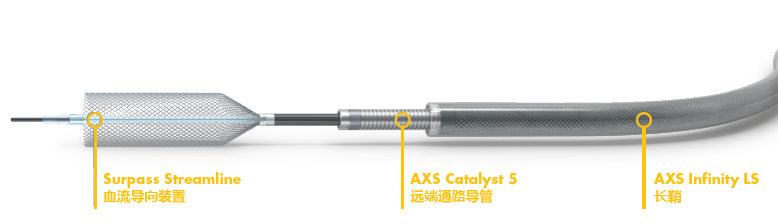

Surpass Streamline

2. 动脉瘤未累及PICA、AICA和基底动脉下段重要穿支血管,拟血流导向装置Surpass Streamline置入治疗。

手术过程

1. Synchro-2微导丝和XT-27微导管将5F Catalyst中间导管引导至椎动脉V4段远端,Synchro-2微导丝携带Surpass Streamline 4.0*30mm进入5F Catalyst,固定Surpass Streamline推送杆,回撤Surpass Streamline外管,在5F Catalyst内释放FD头端一小段;固定支架系统,回撤5F Catalyst,使支架头端部分释放于载瘤动脉内(图9和视频2)。

图9 5F Catalyst中间导管送入Surpass Streamline进行释放;视频2 5F Catalyst中间导管送入Surpass Streamline进行释放。

2. 发现支架前段突入近基底动脉,故回收支架,调整位置后重新释放

视频3 Surpass Streamline进行释放

3. 完全释放支架后,支架近端贴壁稍欠理想,导丝成袢,“按摩”后贴壁改善

视频4 微导丝按摩支架近心端

4. “按摩”后再次造影示支架打开及贴壁较前明显改善,标准正侧位造影(图10)

图10 Surpass Streamline支架植入后左椎动脉造影

5. 术后DynaCT提示支架贴壁良好(视频5和图11)

视频5 微导丝按摩支架近心端

图11 3D图形融合显示 Surpass Streamline支架贴壁良好

术者体会

Surpass Streamline的整体输送性能良好,易于回收,释放稳定。即使遇到在头端定位不准或支架前跳等情况,仍然可以很方便回收并重新定位释放。

Surpass Streamline支架在5F Catalast中预释放,是一种保证支架稳定、成功释放的双保险技术。这也要求将5F Catalast送至动脉瘤以远,对通路提出了更高的要求,好在5F Catalyst 跟踪性、支撑性都非常好。

与其他FD类似,Surpass Streamline支架同样要求远端释放在平顺的血管段,而且近端在推挤下会短缩。因此,在支架型号选择时要充分考虑上述因素,选择足够长的合适规格支架。

Surpass Streamline径向力更大,网孔更密,带来的好处是贴壁好,导流作用强。较适合后循环VA的动脉瘤治疗,更多临床疗效的结果期待随访。